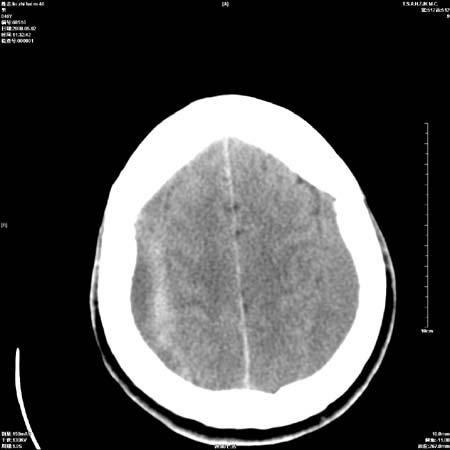

男性   46岁   头晕头痛一周    无任何外伤史    有高血压病史

亚急性硬膜下血肿

考虑双侧慢性硬膜下出血

支持双侧慢性硬膜下血肿。

应该是亚急性(3天——3周)硬膜下出血

亚急性硬膜下血肿;典型。